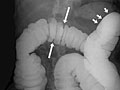

• In an air-contrast or double-contrast study, the colon is first filled with barium, and then the barium is drained out. This leaves only a thin layer of barium on the wall of the colon. The colon is then filled with air. This provides a detailed view of the inner surface of the colon. It makes it easier to see narrowed areas (strictures), diverticula, and swelling.

• Sacs in the colon wall (diverticulosis).